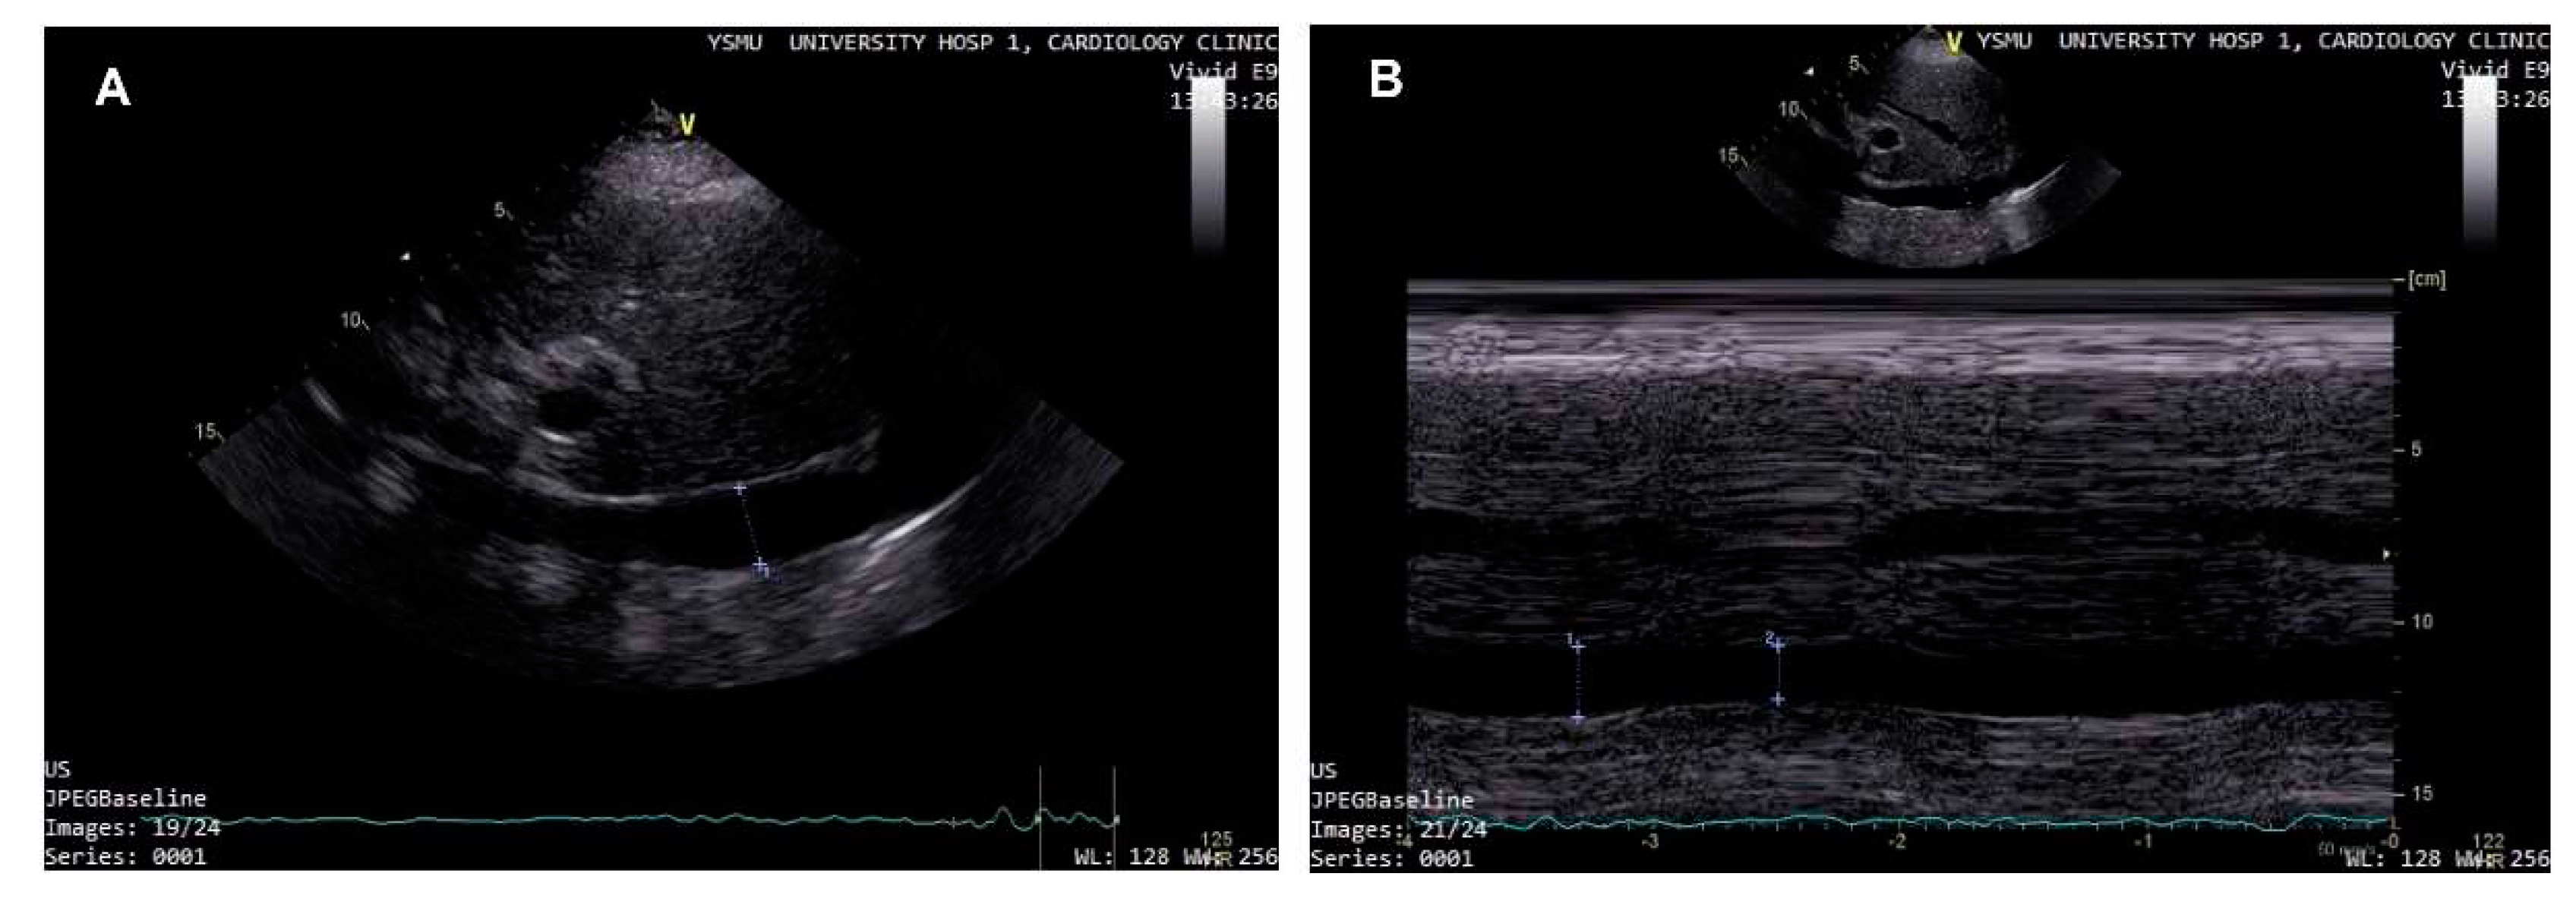

- Pellicori, P.; Carubelli, V.; Zhang, J.; et al. IVC Diameter in patients with chronic heart failure: relationships and prognostic significance. JACC Cardiovasc Imaging. 2013, 6, 16–28. [Google Scholar] [CrossRef]

- Kircher, B.J.; Himelman, R.B.; Schiller, N.B. Noninvasive estimation of right atrial pressure from the inspiratory collapse of the inferior vena cava. Am J Cardiol. 1990, 66, 493–6. [Google Scholar] [CrossRef] [PubMed]

- Nath, J.; Vacek, J.L.; Heidenreich, P.A. A dilated inferior vena cava is a marker of poor survival. Am Heart J. 2006, 151, 730–5. [Google Scholar] [CrossRef] [PubMed]

- Curbelo, J.; Rodriguez-Cortes, P.; Aguilera, M.; Gil-Martinez, P.; Martín, D.; Fernandez, C.S. Comparison between inferior vena cava ultrasound, lung ultrasound, bioelectric impedance analysis and natriuretic peptides in chronic heart failure. Curr Med Res Opin. 2019, 35, 705–713. [Google Scholar] [CrossRef] [PubMed]

- Dalen, H.; Gundersen, G.H.; Skjetne, K.; et al. Feasibility and reliability of pocket-size ultrasound examinations of the pleural cavities and vena cava inferior performed by nurses in an outpatient heart failure clinic. Eur J Cardiovasc Nurs. 2015, 14, 286–293. [Google Scholar] [CrossRef] [PubMed]

- Gundersen, G.H.; Norekval, T.M.; Haug, H.H.; et al. Adding point of care ultrasound to assess volume status in heart failure patients in a nurse-led outpatient clinic. A randomised study. Heart. 2016, 102, 29–34. [Google Scholar] [CrossRef]

- Saha, N.M.; Barbat, J.J.; Fedson, S.; Anderson, A.; Rich, J.D.; Spencer, K.T. Outpatient Use of Focused Cardiac Ultrasound to Assess the Inferior Vena Cava in Patients With Heart Failure. Am J Cardiol. 2015, 116, 1224–1228. [Google Scholar] [CrossRef]

- Curbelo, J.; Aguilera, M.; Rodriguez-Cortes, P.; Gil-Martinez, P.; Fernandez, C.S. Usefulness of inferior vena cava ultrasonography in outpatients with chronic heart failure. Clin Cardiol. 2018, 41, 510–517. [Google Scholar] [CrossRef]

- Lee, H.F.; Hsu, L.A.; Chang, C.J.; et al. Prognostic significance of dilated inferior vena cava in advanced decompensated heart failure. Int J Cardiovasc Imaging. 2014, 30, 1289–1295. [Google Scholar] [CrossRef]